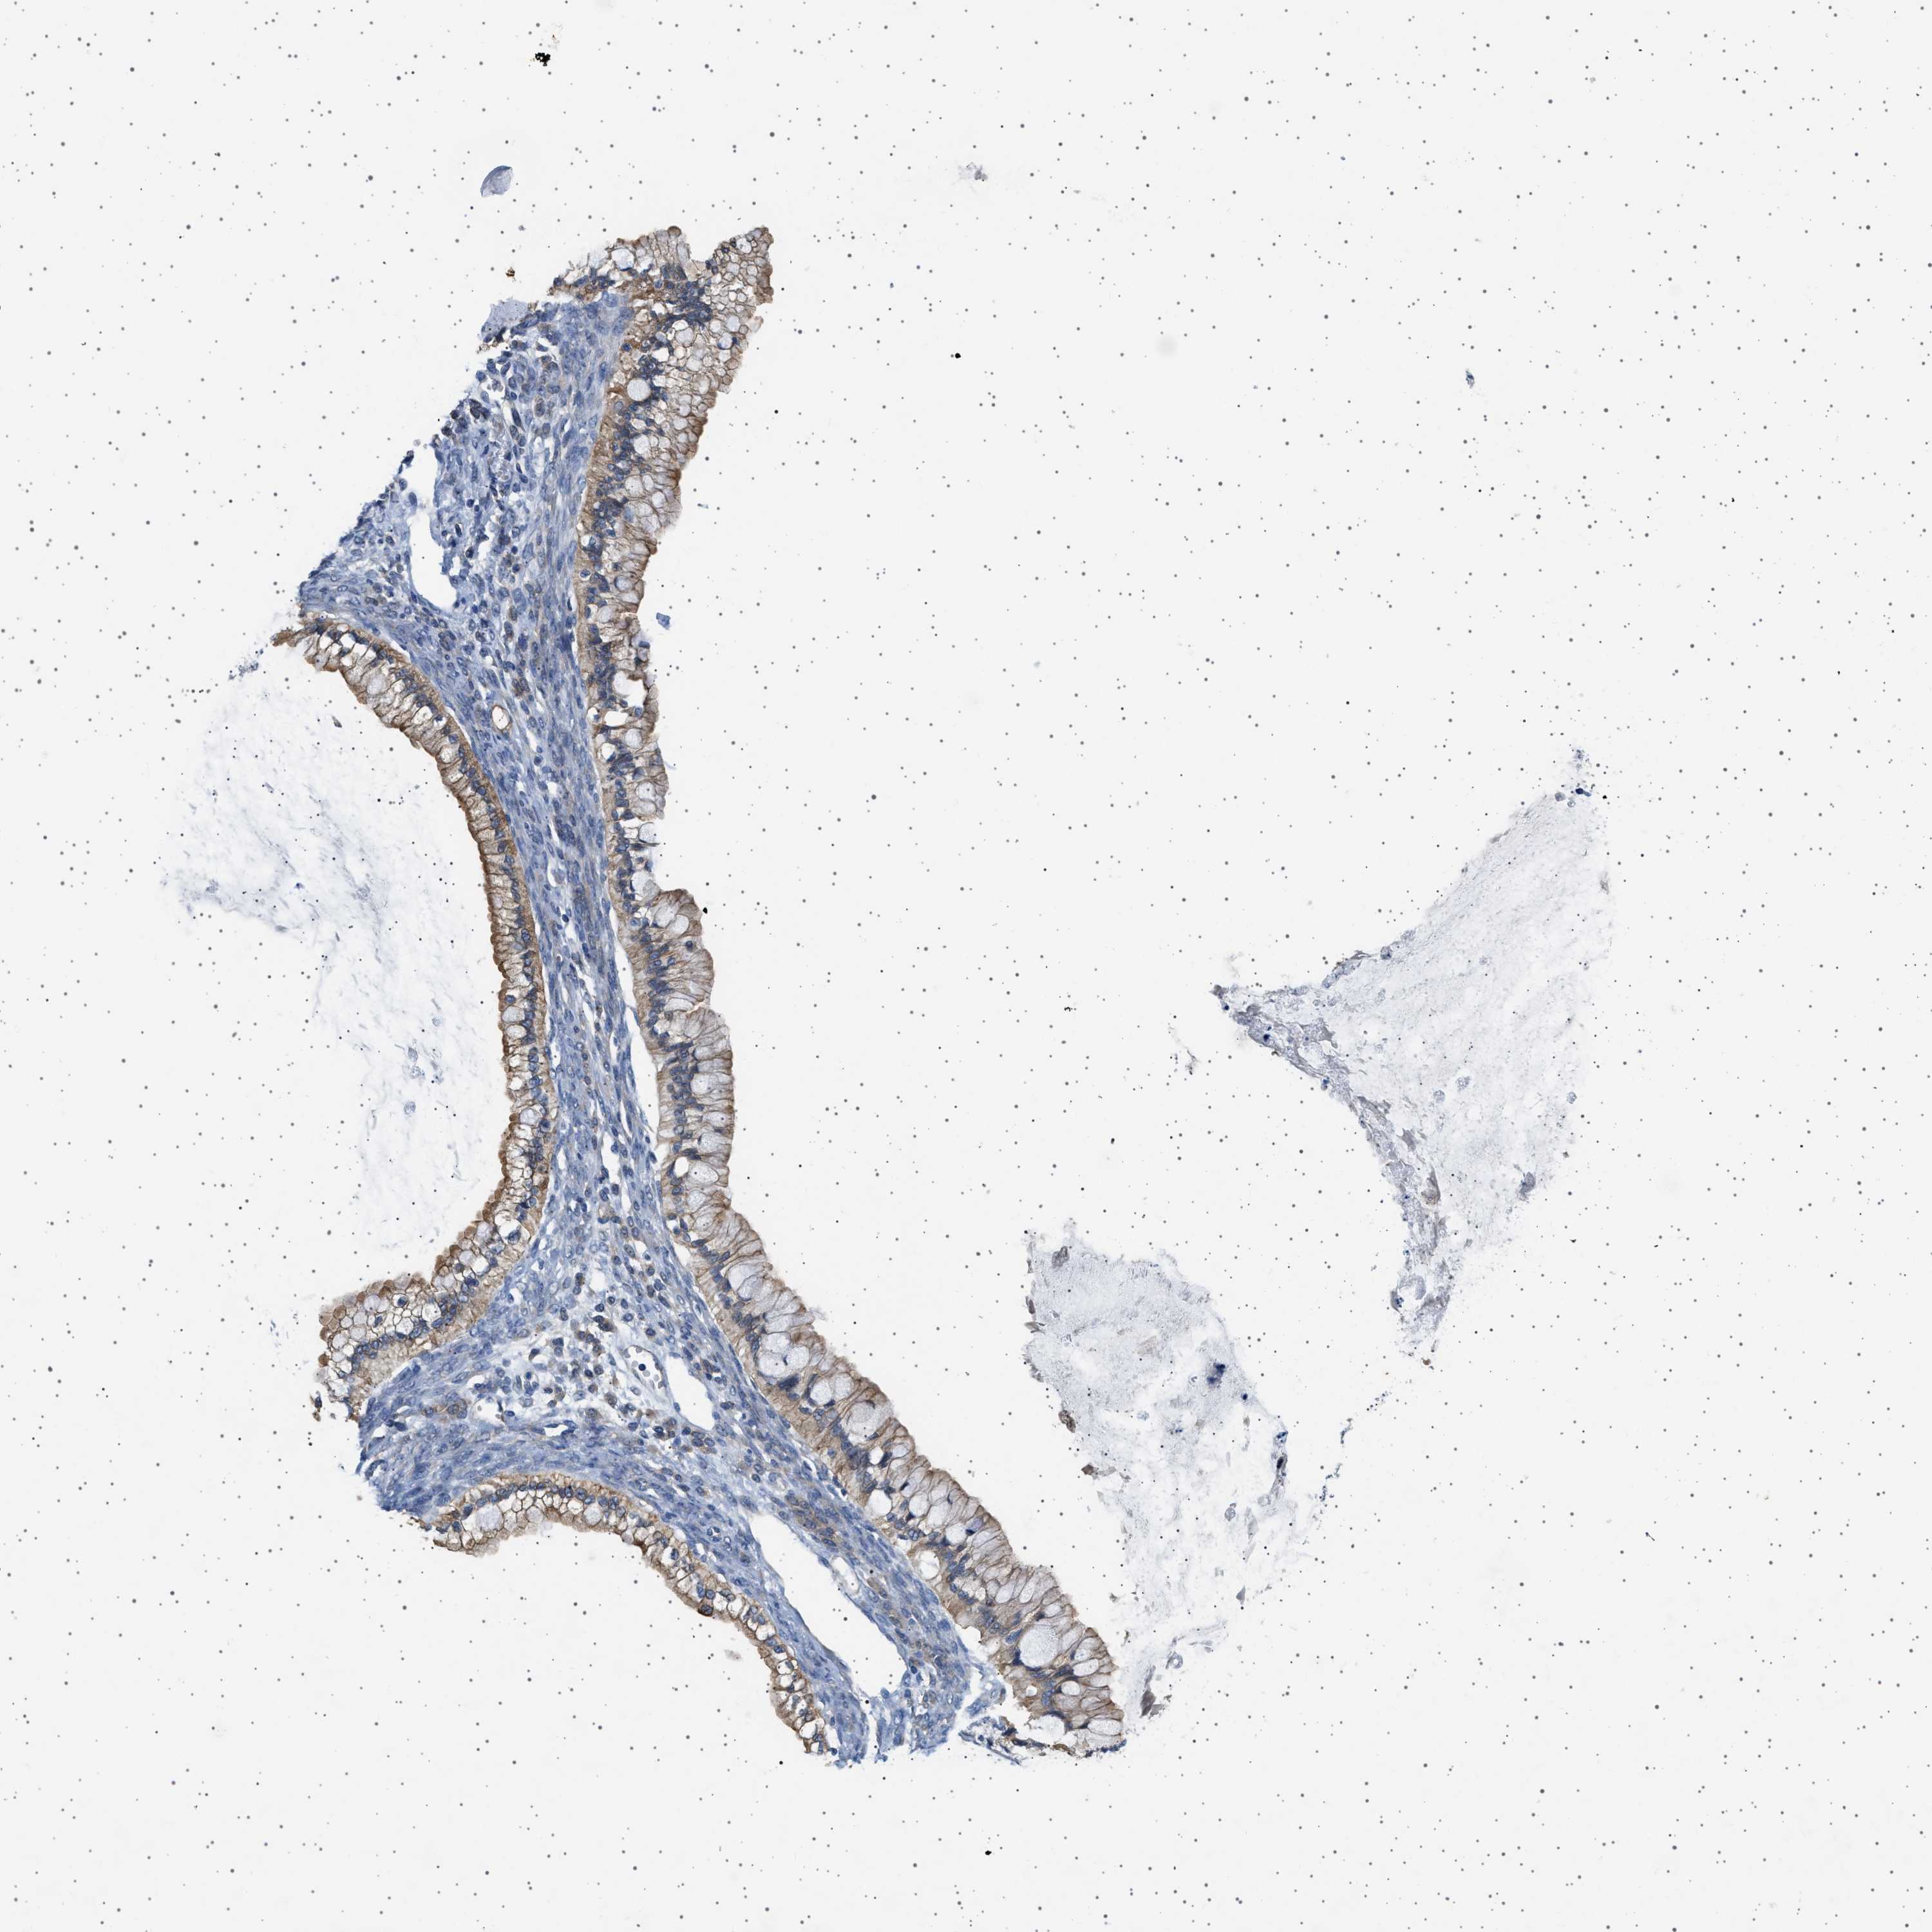

OVARIAN CANCER - Protein expressioni

A mouse-over function shows sample information and annotation data. Click on an image to view it in a full screen mode. Samples can be filtered based on level of antibody staining by selecting one or several of the following categories: high, medium, low and not detected. The assay and annotation is described here.

Note that samples used for immunohistochemistry by the Human Protein Atlas do not correspond to samples in the TCGA dataset.

Antibody stainingi

Antibody staining in the annotated cell types in the current human tissue is reported as not detected, low, medium, or high, based on conventional immunohistochemistry profiling in selected tissues. This score is based on the combination of the staining intensity and fraction of stained cells.

Each image is clickable and will lead to virtual microscopy that enables deeper exploration of all samples and also displays staining intensity scores, fraction scores and subcellular localization as well as patient and tissue information for each sample.

Antibody HPA018096

Cystadenocarcinoma, serous, NOS

Carcinoma, endometroid

Cystadenocarcinoma, mucinous, NOS

Carcinoma, NOS